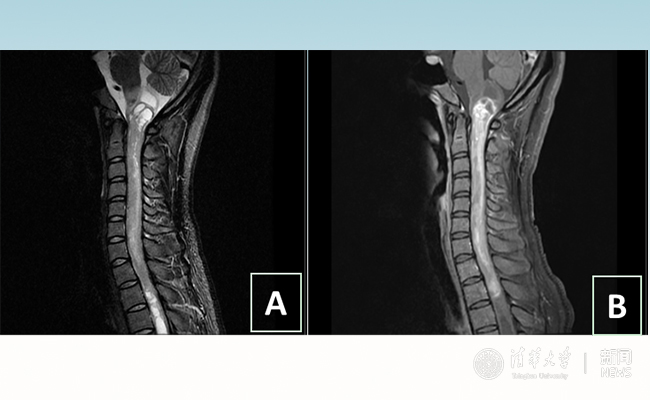

2018.01拯救“90后”女孩 清华长庚神经外科切除20多公分髓内肿瘤

“愿得韶华刹那,开得满树芳华。”27岁的患者小甜(化名)在beat365英国官方网站附属北京清华长庚医院成功进行了手术,神经外科主任王贵怀为其切除了自延髓至胸髓的长达20余公分的脊髓内肿瘤。1月9日,小甜顺利出院,再续芳华!